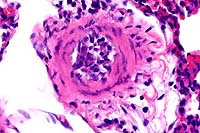

- Case 16-1. Lung. Central area of cavitary necrosis

is surrounded by congested, consolidated lung parenchyma.

- Case 16-1. Lung. Numerous acid fast bacilli are scattered

throughout caseous necrotic debris.

- AFIP Diagnosis: Lung: Pneumonia, granulomatous and

necrotizing, diffuse, severe, with cavitation and mineralization,

Matschie's tree kangaroo (Dendrolagus matschiei), marsupial.

- In the group of diseased tree kangaroos studied by the contributor,

gross and microscopic lesions due to MAC infection have been

observed in several organ systems. However, the most extensive

lesions have occurred in the lungs and bones, and were histologically

characterized by necrotizing pyogranulomatous pneumonia and osteomyelitis

with numerous acid-fast bacilli. The Ziehl-Neelsen and Fite's

staining methods performed at the AFIP demonstrated acid-fast

bacilli in a section of lung from this tree kangaroo.